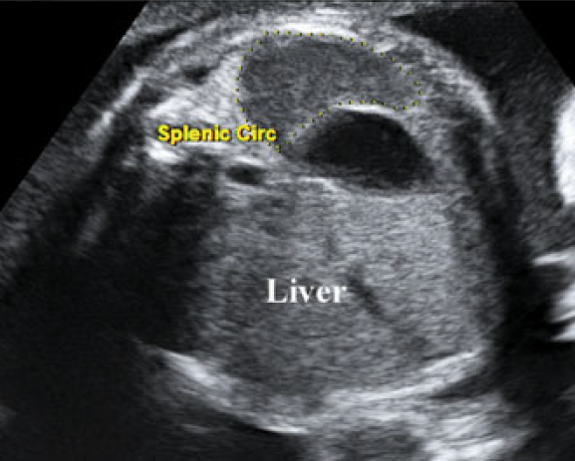

脾周长图解

上腹部横切面于胃泡后方显示等回声弯月形脾脏回声,描记法测量脾周长